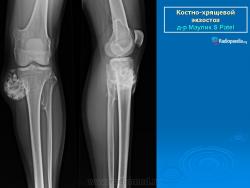

Костно-хрящевые экзостозы (остеохондрома).

Костно-хрящевые экзостозы